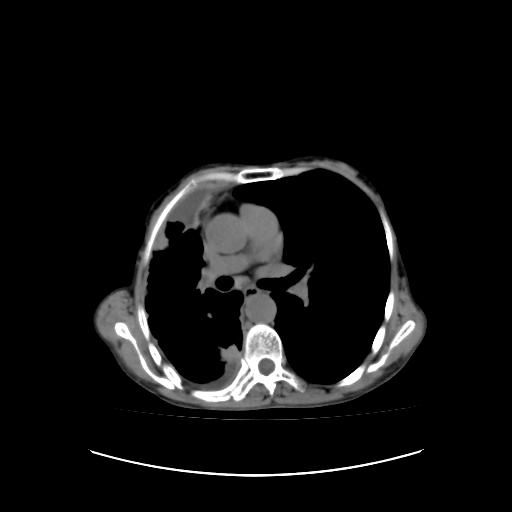

标题: CT16930:女 59 胸痛6个月 胸水脱落细胞学见瘤细胞 [打印本页]

标题: CT16930:女 59 胸痛6个月 胸水脱落细胞学见瘤细胞

可见多发肺内病灶,且胸膜病灶较多有圆球状而非丘状,多考虑胸膜转移瘤伴胸腔积液,右侧胸廓缩小固定,且部分病灶呈丘状,尚不除外恶性胸膜间皮瘤伴肺内转移

右侧胸膜增厚,局部呈结节状增厚,右侧胸腔少量积液。双肺未见确切肿块影。纵隔未见淋巴结肿大。气管、支气管通畅。考虑右侧胸膜间皮瘤(恶性?)可能性大。不除外癌性胸膜炎。

恶性胸膜间皮瘤伴肺内转移可能性大;或胸膜、肺内均为转移瘤,左肺下叶亦见多发小结节影。

右侧胸廓塌陷,右侧胸膜广泛增厚并见多发胸膜结节,右侧少量胸腔积液并包裹。

右侧广泛胸膜增厚,局部呈结节状增厚,右侧胸腔少量积液。双肺未见确切肿块影。纵隔未见淋巴结肿大。气管、支气管通畅。考虑右侧胸膜间皮瘤(恶性?)可能性大。支持!

右侧胸膜转移瘤,原发灶可能就在在右肺,另外建议检查右侧乳腺.

右胸腔结节均考虑来自胸膜(部分来源于叶裂),考虑胸膜间皮瘤或转移瘤.